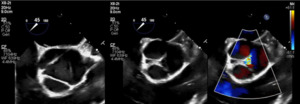

Brain and neck magnetic resonance angiography (MRA) showed no acute or significant vascular abnormality. Transesophageal echocardiogram showed severe aortic regurgitation, trileaflet thickened aortic valve, enlarged ascending aorta 45 mm, normal left ventricular systolic function and patent foramen ovale (Figure 1, Figure 2 and Figure 3). Calculated aorta size index (aortic size cm/body surface area m2) was moderate-severely increased, 2.7 cm2/m2. Mild immobile atherosclerosis of the aorta was noted.